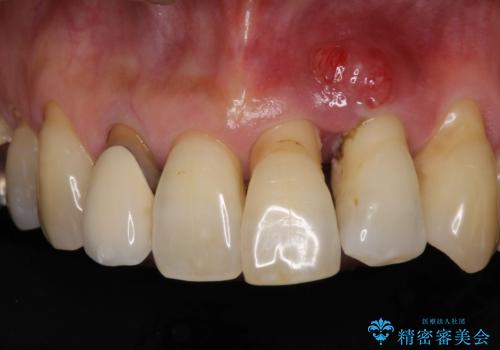

- 前歯の歯肉の腫れを気にして来院された患者様です。

前歯は抜歯が必要であったので、抜歯を行い、その後歯肉移植をおこなった上でオールセラミックブリッジによる補綴治療を行うこととしました。